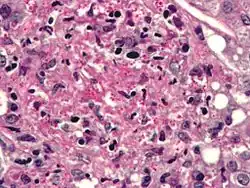

Histoplasma

Genus: Histoplasma